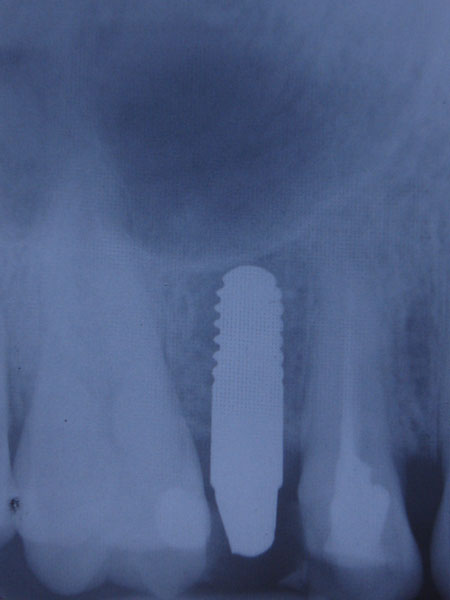

Un rol important in tratamentul cu implanturi dentare il are calitatea acestora, din ce si cum sunt fabricate. Pentru fabricarea implanturilor dentare Firma Bredent foloseste Ti de grad 4, cel mai pur titan utilizat in medicina, fara alte metale, evitand astfel riscul aparitiei complicatiilor.

De asemenea titanul este dublu laminat la rece, procedeu prin care se obtine o rezistenta mecanica superioara altor implanturi dentare care folosesc aliaje ale titanului (grad 1, 2, 3, 5 etc). In timpul procesului de fabricatie o atentie deosebita este acordata indepartarii reziduurilor de orice fel (uleiuri, acizi, substante folosite in producerea oricarui tip de implant dentar). Toate elementele utilizate ulterior in tratamentul protetic pe implanturi dentare sunt de asemenea fabricate din titan de grad 4. Prin toate acestea, numarul esecurilor este redus la minim.

Bredent produce aceste implanturi dentare in Germania, respectand standardele de calitate din Germania.